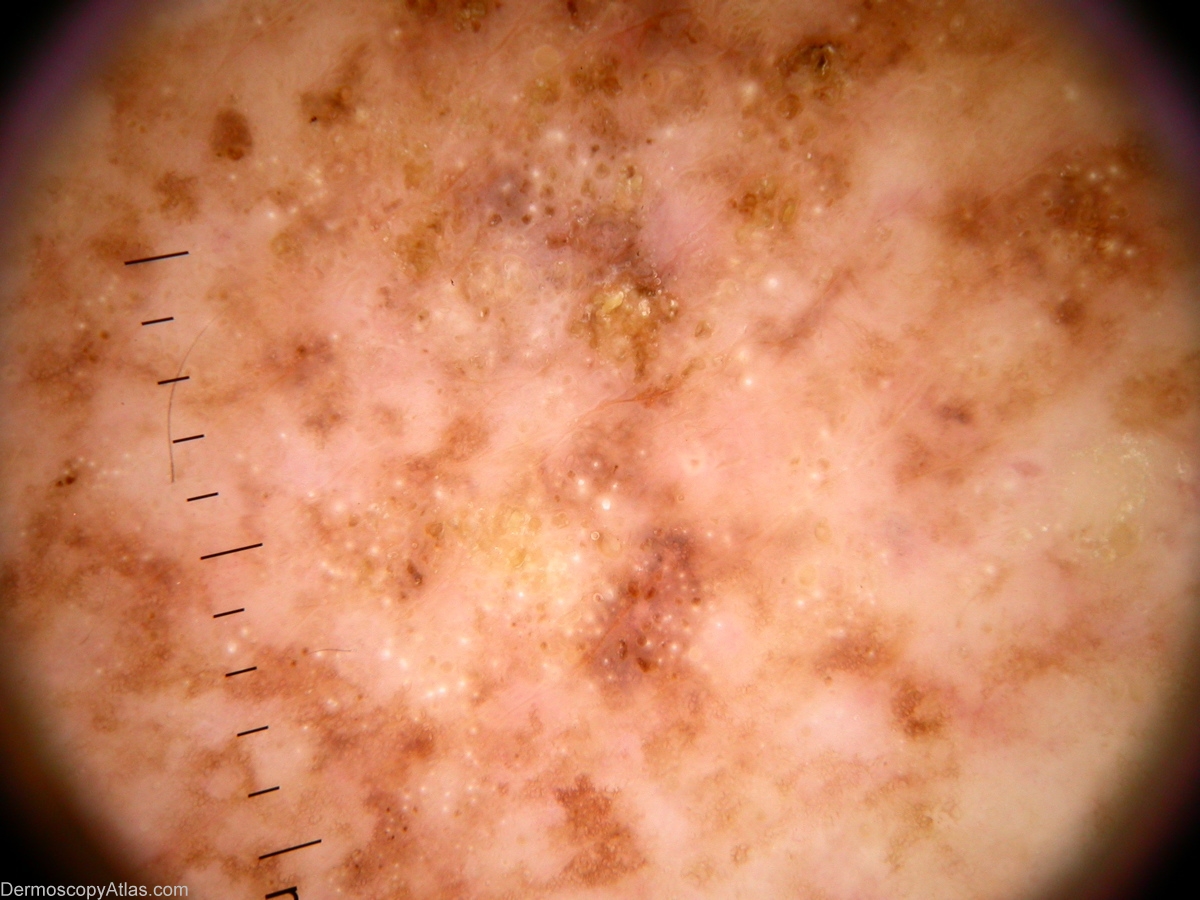

Image Number #2535 (Seborrhoeic keratosis)

Site: Back

Diagnosis: Seborrhoeic keratosis

Sex: M

Age: 72

Type: Dermlite Non Polarised

Submitted By: Alan Cameron